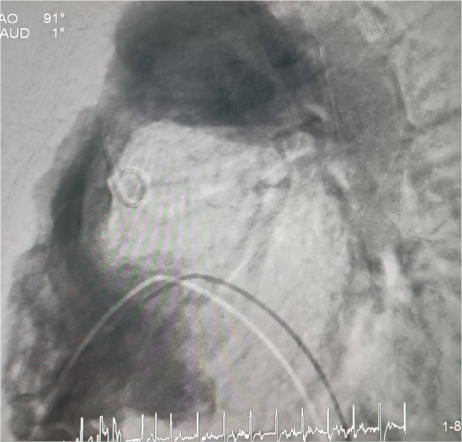

– Нам доступны клапаны с размерной линейкой от 2 до 3-х сантиметров. Клапан можно имплантировать, если размер выводного тракта и самого кондуита – места, куда надо ставить клапан – от 2 до 3-х см. Если диаметр меньше, то клапан будет кальцинироваться, тромбироваться, створки перестанут работать и снова произойдёт стеноз, – пояснил рентгенэндоваскулярный хирург Михаил Комиссаров. |

У пациента из Луганской Народной Республики просвет ранее имплантированного кондуита составлял 1,5 сантиметра, поэтому рентгенхирурги на первом этапе расширили его методом баллонной дилатации. При этом был риск разрыва сосуда, поэтому, чтобы избежать возможных осложнений, медики сначала имплантировали стентграфт – металлический каркас, покрытый герметичным полимером. Просвет кондуита удалось расширить до необходимого диаметра. Затем через бедренную вену хирурги доставили к сердцу искусственный биологический клапан лёгочной артерии Myval индийского производства.

Сложную операцию провела команда врачей Педиатрического университета - рентгенэндоваскулярные хирурги Михаил Комиссаров, Владимир Приворотский и Иван Алешин. Неоценимую помощь медикам СПбГПМУ оказал заведующий отделением рентгенэндоваскулярных методов диагностики и лечения Городской многопрофильной больницы №2 Евгений Шлойдо.